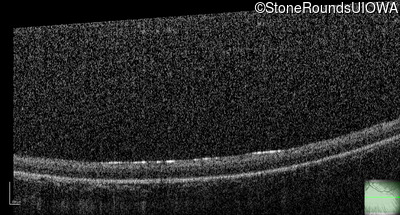

Optical Coherence Tomography - Left - No Light Perception

Exemplar / OCT Stack